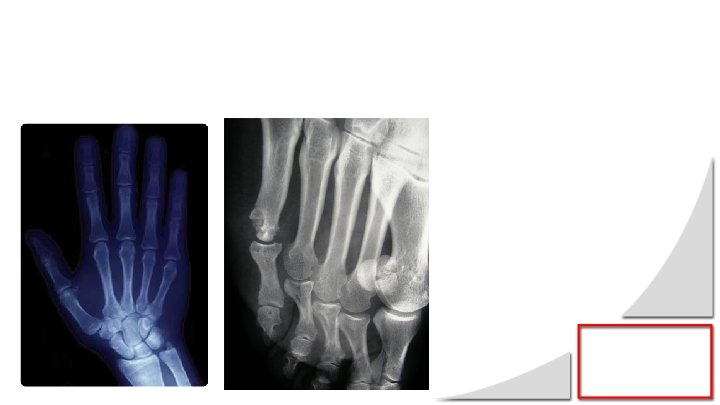

Question 2 Des radiographies ont été pratiquées à la demande de son médecin traitant (Iconographies 1 et 2). Analysez les. 10

Question 2 • Radiographie de la main - Tuméfaction des parties molles (1 pt) - Déminéralisation épiphysaire en bande (2 pts) - NB/ Pas d’érosions juxta-articulaires du carpe ni des doigts • Radiographie de l’avant-pied - Erosion de la 5ème tête métatarsienne (3 pts) très évocatrice de PR 12